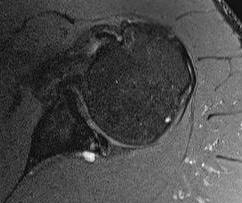

Spinoglenoid Cyst

MRI

Spinoglenoid cyst with SLAP tear and posterosuperior labral tear